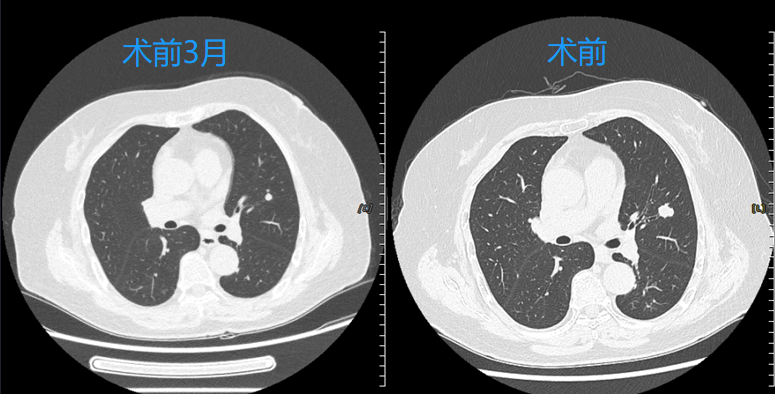

精准微创,点亮希望

近日,清华大学附属垂杨柳医院呼吸与危重症医学科成功为一位老年女性气管腺样囊性癌肺转移患者实施了经支气管镜肺转移瘤冷冻消融术。该技术的应用标志着医院在肺部肿瘤...[详情]